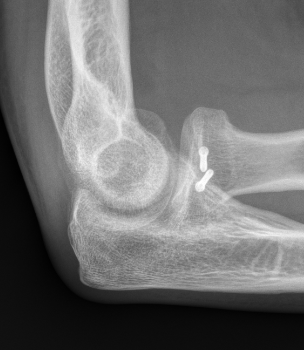

Radial Head Fixation

Indication

Significant fragment displacement

Reconstructable

Technique

Identify safe zone for implants

- posterolateral portion of cartilage / yellow and thinner, non articulating cartilage

- 90o arc between radial styloid and Lister's tubercle

- 2.5 or 3.5 headless compression screws

Complications

PIN injury

Intra-articular screws

Hardware failure

Heterotopic ossification

AVN

Non union

Radial head fragment nonunion